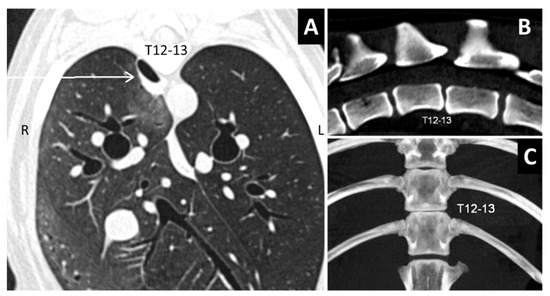

Figure 4.

(A). Type 2 pulmonary laceration (arrow) in a traumatized dog with T12-13 subluxation. (B,C) Sagittal and dorsal views of the spine. Note the T12–13 misalignment in the sagittal view (B) with reduced intervertebral space (C).